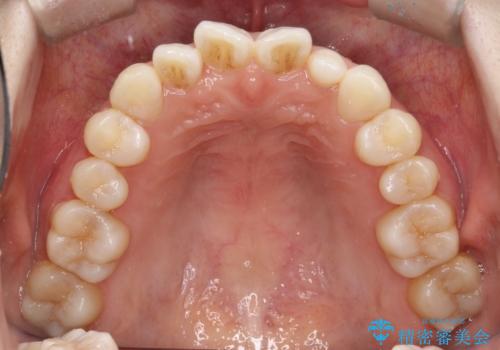

【インビザライン】矮小歯を有する方の治療②

- 前歯の凸凹を主訴に来院されました。

左上の前歯が元々小さいため、前歯の真ん中が揃わないことを伝えた上で矯正治療を開始しています。

スペースを作るために遠心移動ろIPRをおこなて治療を行いました。